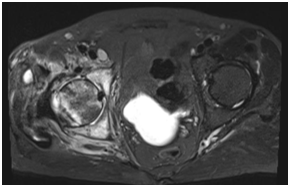

Radiographic study with MRI of the right hip without contrast showed right hip moderate-sized effusion with diffusely scattered soft tissue/intramuscular fluid and edema extending along the right iliac wing with diffuse marrow edema involving the right pelvis, right femoral head/neck region compatible with osteomyelitis and septic arthritis. (Figure 1).